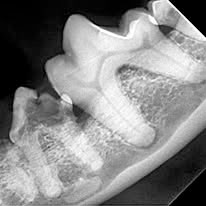

È assolutamente necessario eseguirla prima di raggiungere situazioni patologiche gravi, alcune molto spesso individuabili solo con radiografie dentali :